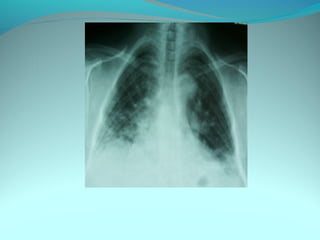

Opacité occupant la partie externe du 1/3 infer du poumon droit

dense et homogene ovalaire de 8cm de grand axe vertical

La limite externe se confend avec une opacité d’environ 1cm comble

les coupole costodiaphragmatique droit

Limitée a sa partie sup par la petit sessure qui est epaisse et pas de

lyse costale

 DIAGNOSTIC :DIAGNOSTIC :

 1_1_cancer bronchique droit( d epaississement)

 2_2_ kyste hydatique au stade sain